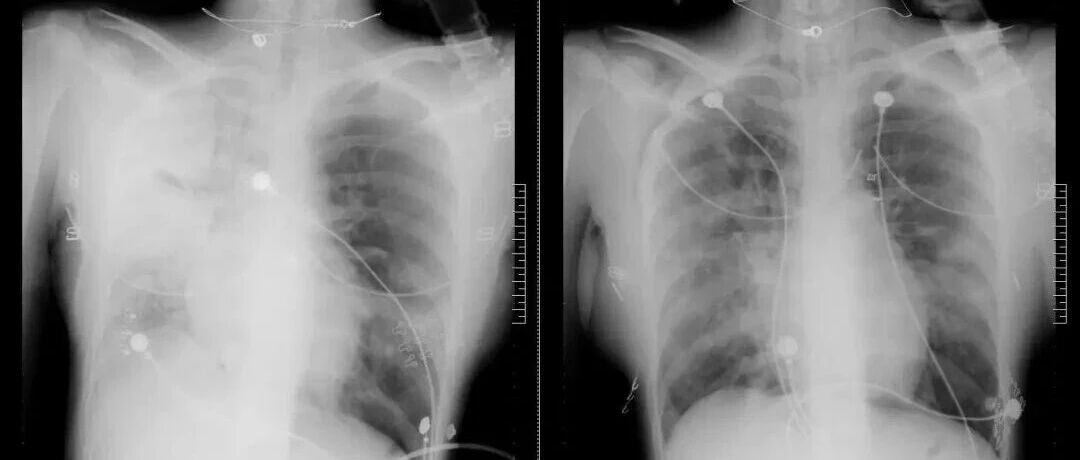

流感可能引发肺炎、心肌炎、脑炎等严重并发症。老人、孩子、孕妇等重症高风险人群加强个人防护,减少感染风险。每年接种流感疫苗。出现症状,不要自行判断,应通过病原学检测明确诊断,实现早诊早治。出现以下情况,应立即就医:高热不退超过3天。呼吸急促、胸闷、胸痛、喘憋。婴幼儿嗜睡、精神萎靡、烦躁、拒绝进食。